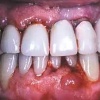

Krooniline parodontiit

Krooniline parodontiit on mikroobide poolt põhjustatud hammaste tugikudede põletik, mille tulemusena tekib progresseeruv alveolaarluu (nähtav röntgenograamil) ja periodontaalligamendi destruktsioon, igemetaskute moodustumine, igeme retsessioon või mõlemad kahjustused kombineeritult. Krooniline parodontiit on...